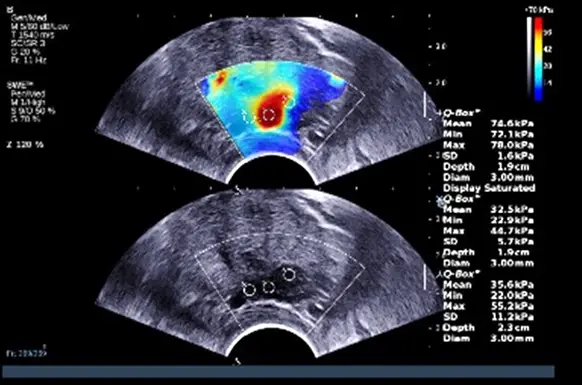

本題提供兩張經直腸前列腺超音波(Transrectal ultrasound, TRUS)的影像:

- 上方影像(Color map overlay):在灰階 B-mode 影像上疊加了彩色的彈性圖(elastogram)。右側有顏色量表(color scale),單位標示為「kPa」,顏色由藍色(代表軟組織,數值低)漸層至紅色(代表硬組織,數值高)。畫面中央的感興趣區域(Region of Interest, ROI)也就是圖中的「Q-Box 1」,放置在一個呈現紅色的高硬度病灶上,右側數據顯示其平均硬度(Mean)為 74.6 kPa。

- 下方影像(B-mode 影像):為原始的灰階超音波影像,可以看到左後方的 peripheral zone 有一個低回音(hypoechoic)的病灶。圖中放置了另外兩個 Q-Box(Q-Box 2 與 3),測得的平均硬度分別為 32.5 kPa 與 35.6 kPa,這些數值代表周圍相對正常的軟組織。

題目明確指出測量結果的單位為「kPa」(千帕),且影像中展示了將組織硬度視覺化的彩色對應圖(color map),同時 B-mode 顯示了前列腺 peripheral zone 的低回音病灶。在醫學超音波中,使用 kPa 單位來定量組織特性的技術唯有超音波彈性造影(具體為 Shear Wave Elastography)。前列腺癌細胞的增生與間質纖維化會導致局部組織變硬,因此在彈性造影下會呈現高 kPa 數值(如圖中 74.6 kPa 的紅色區域),這與周圍正常偏軟的腺體組織形成強烈對比。因此,正確答案為 (B)。